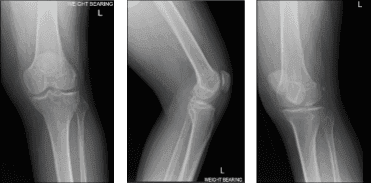

El paciente presentado hoy es un hombre, de 36 años. Se queja de que le duele muchísimo la rodilla izquierda. También presentó el resultado de su radiografía. Existen cambios degenerativos osteoartríticos leves, pero no se han encontrado fracturas agudas. Había probado una gestión conservadora, pero sin ningún beneficio.

Resonancia magnética de rodilla izquierda

Acordamos hacer una resonancia magnética de 3 Tesla de la rodilla izquierda para finalizar el diagnóstico. También hablamos de opciones de tratamiento, incluyendo fisioterapia, inyecciones y también cirugía. El paciente seguirá haciendo terapia de hielo/calor porque le ayuda un poco con la condición de rodilla.

Tras una semana, los resultados de la resonancia magnética recibidos y comentados con el paciente mostraron que, además del derrame articular, se observan algunos cambios degenerativos en el compartimento patelofemoral y en la parte posterior de la meseta tibial medial, que podrían estar relacionados con el SNP focal.